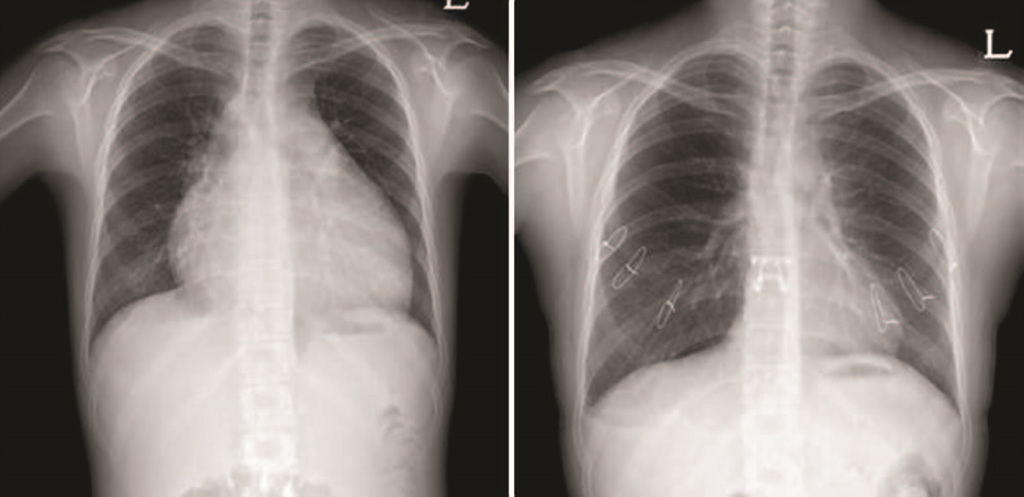

144 국내 첫 생체 폐이식 성공